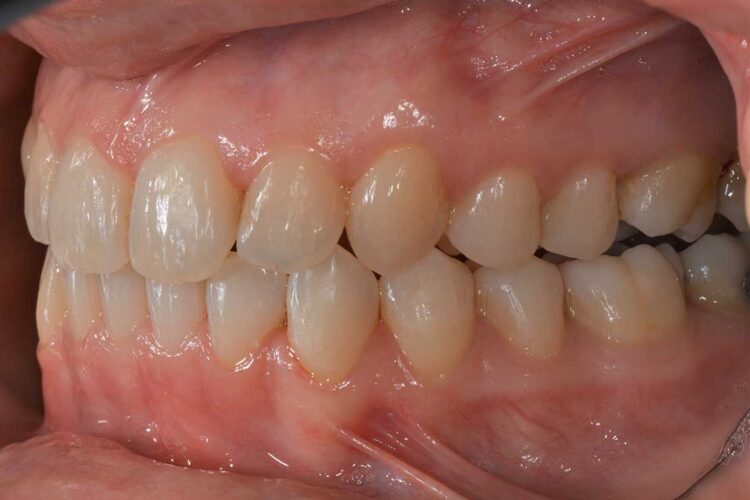

Ortodonzia allineatori – caso clinico 1